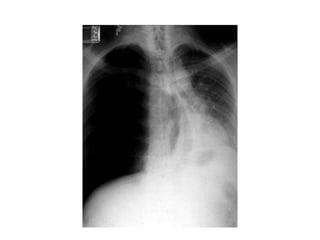

3. TDM thoracique

pleurale

• La TDM thoracique n’est pas nécessaire au

diagnostic mais indiquée si la

symptomatologie évocatrice contraste avec

une RX thorax normale

• Par contre sa pratique est courante pour le

diagnostic étiologique et dans la discussion

d’un geste thérapeutique radical

TDM thoracique

• Elle permet aussi d’apprécier le risque de

récidive en précisant le nombre le volume et

la topographie des bulles

Résultats :

• Le PNO apparaît sous forme d’une plage noire

qui refoule le poumon comparé à un croissant

gazeux